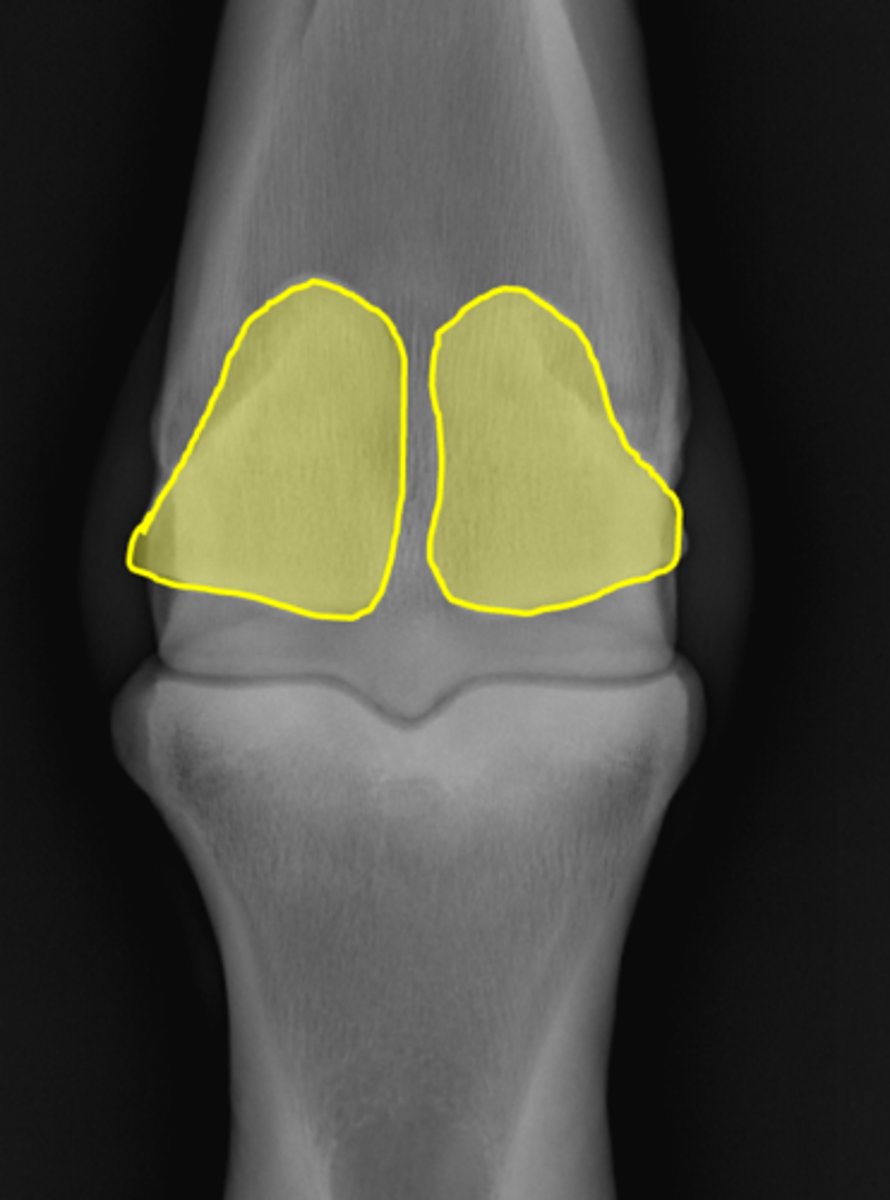

Fetlock joint, DP

ID joint and view

Proximal sesamoid bones

Sagittal ridge

Attachment of collateral ligaments

Proximal sesamoid bones

Palmar process of P1

Condyles of the third metacarpal bone